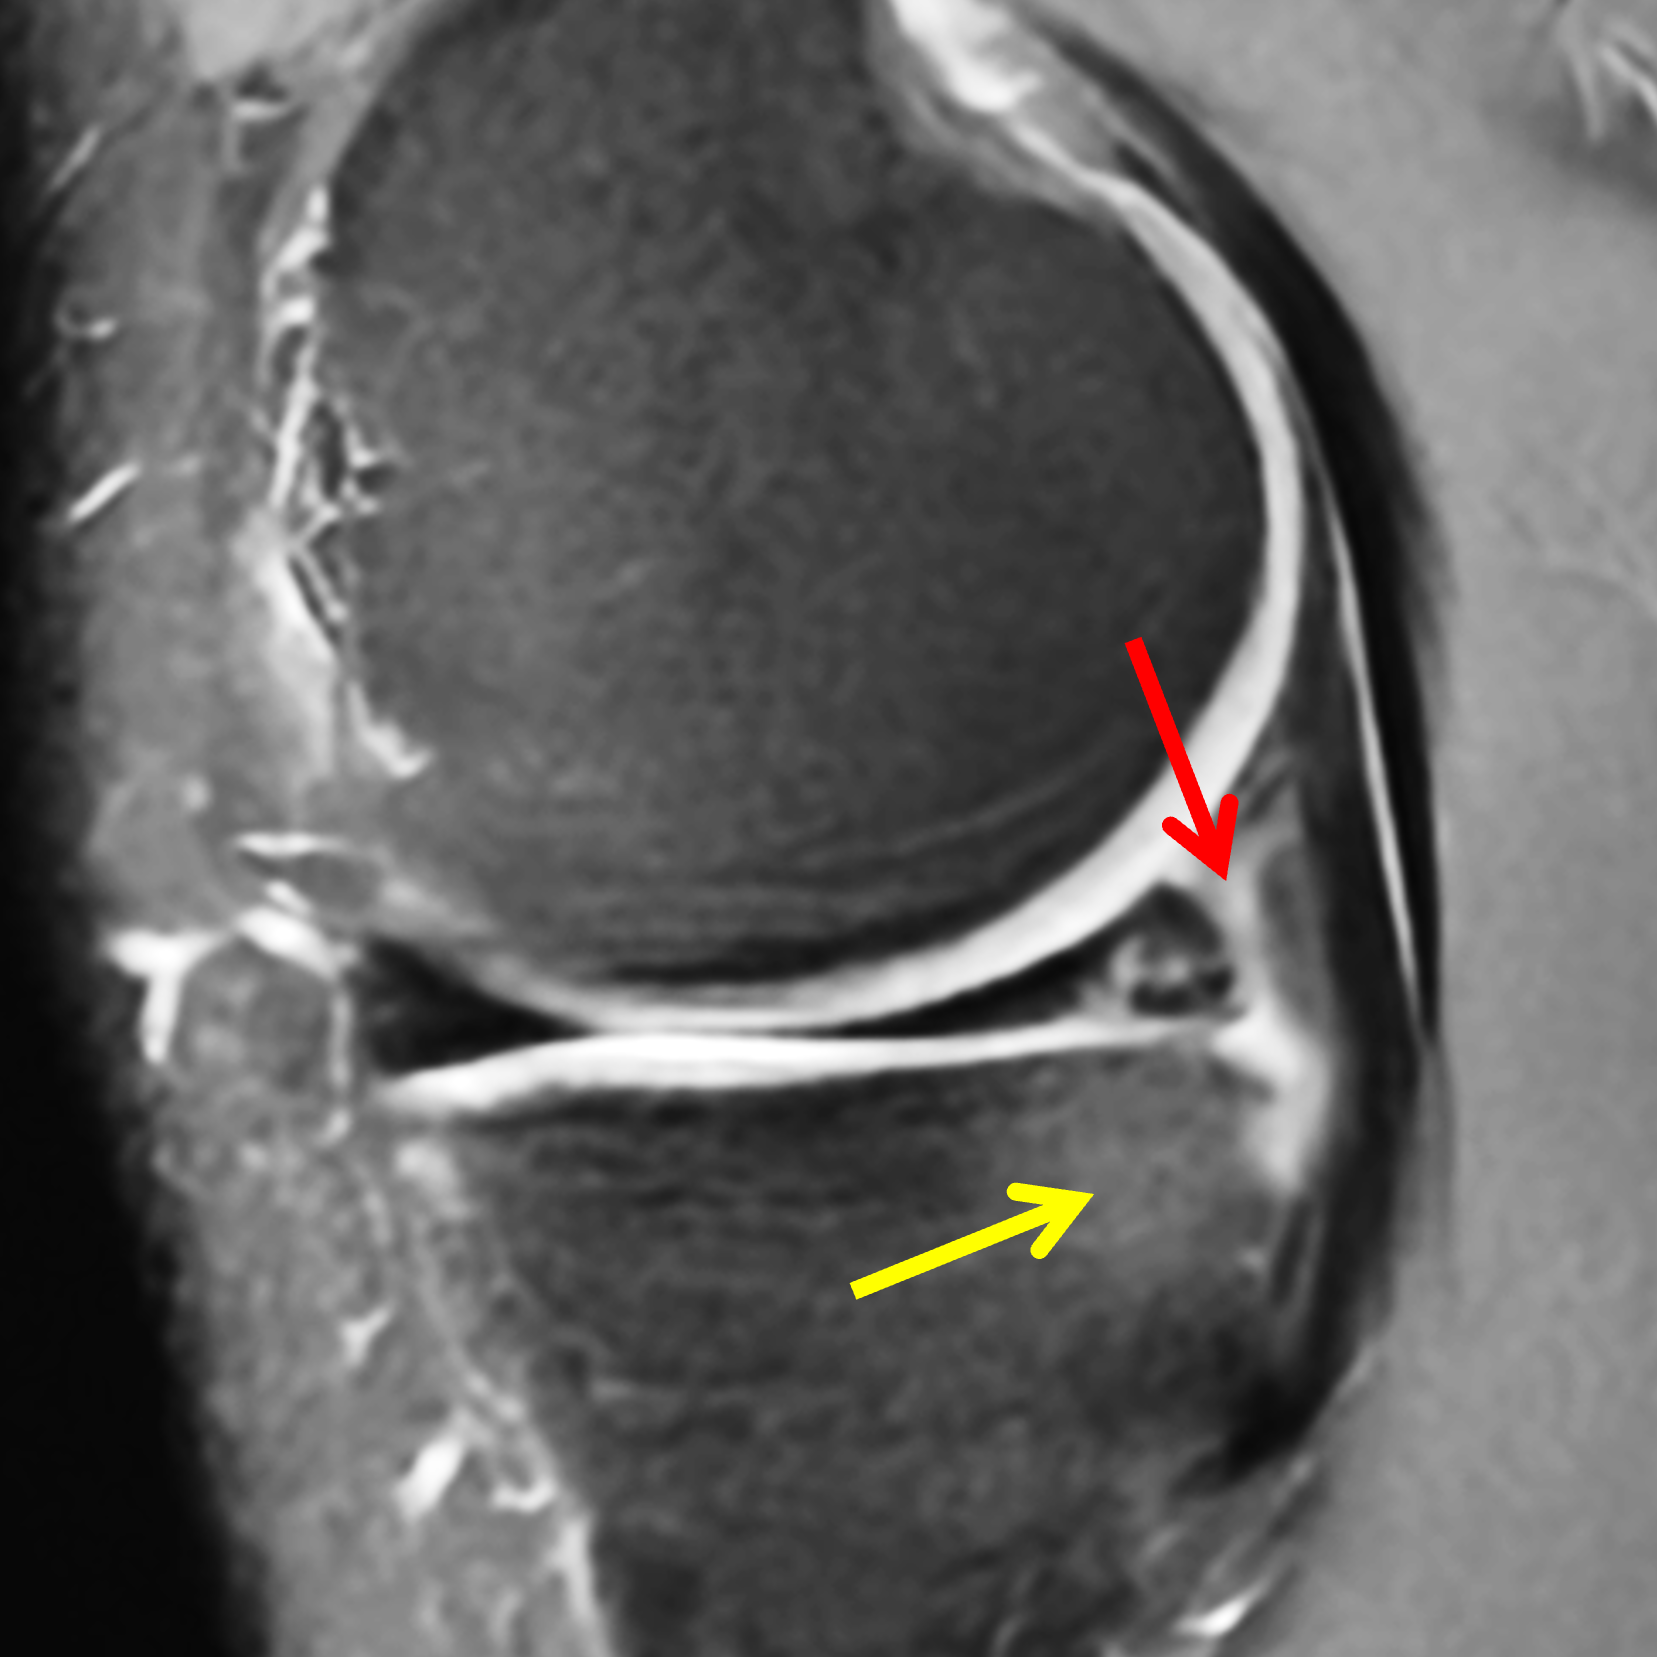

A 19-year-old collegiate baseball player sustained a twisting injury to the knee 3 weeks earlier. Sagittal (1A) proton density-weighted fat-suppressed image through the intercondylar notch, (1B and 1C) proton density-weighted images through the medial compartment, and (1D) fat-suppressed proton density image through the medial compartment are provided. What are the findings? What is your diagnosis?

Figure 2: (2A) Sagittal image through the intercondylar notch shows a complete tear of the anterior cruciate ligament (arrowheads). (2B and 2C) Near the posterior meniscocapsular junction of the medial meniscus, there is disruption of the posterior meniscotibial ligament (red arrow) and irregularity of the posterior meniscocapsular ligament (yellow arrow). (2D) On the fluid-sensitive sequence, linear high signal intensity is interposed between the ligaments and the posterior horn of the medial meniscus (arrowheads).

Anterior cruciate ligament tear with a medial meniscal ramp lesion.